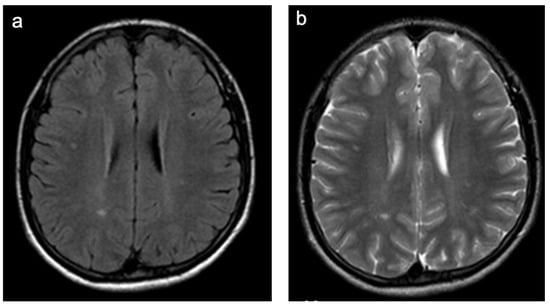

Figure 3. Representative case “Autoimmune disorders”: MS. FLAIR (a), T1W pre- and post-contrast (b,c) sequences. Fifteen-year-old girl diagnosed with MS. MRI shows characteristic ovoid/round lesions with asymmetric distribution abutting the lateral ventricles (periventricular) and touching the cortex (juxtacortical) [19] (a). Contrast-enhancing lesions in T1W post-contrast sequences are considered markers of blood–brain barrier breakdown (c).

Figure 6. Representative case “Non-specific WMSAs”. FLAIR (a) and T2W (b) sequences. Fifteen-year-old girl presenting with a headache. MRI shows non-specific periventricular and subcortical WMSAs. Follow-up scan showed stable lesions (a,b). Patients in this group presented with WMSAs and clinical symptoms that were non-specific for the large number of disorders associated with such abnormalities.